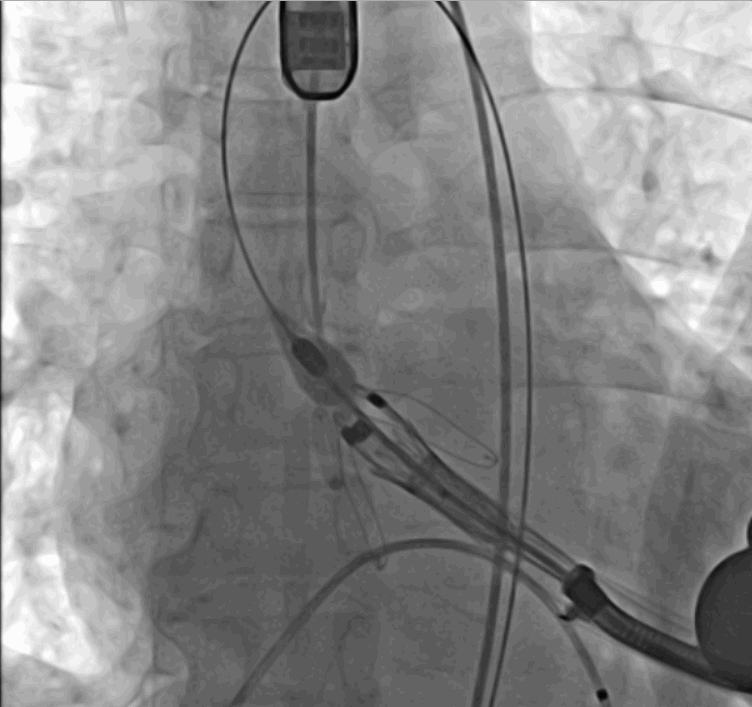

術(shù)中釋放定位鍵后DSA影像圖

術(shù)中瓣膜釋放過(guò)程

手術(shù)采用經(jīng)心尖入路,對(duì)患者進(jìn)行全麻后,在左側(cè)心尖處做3-4cm微創(chuàng)手術(shù)切口,在DSA及超聲引導(dǎo)下手術(shù)順利完成。從導(dǎo)入器械到完成瓣膜置入,僅耗時(shí)約10分鐘。術(shù)后即刻主動(dòng)脈瓣返流程度由術(shù)前大量返流轉(zhuǎn)為消失,患者于導(dǎo)管室拔除氣管插管,次日由ICU轉(zhuǎn)入普通病房。